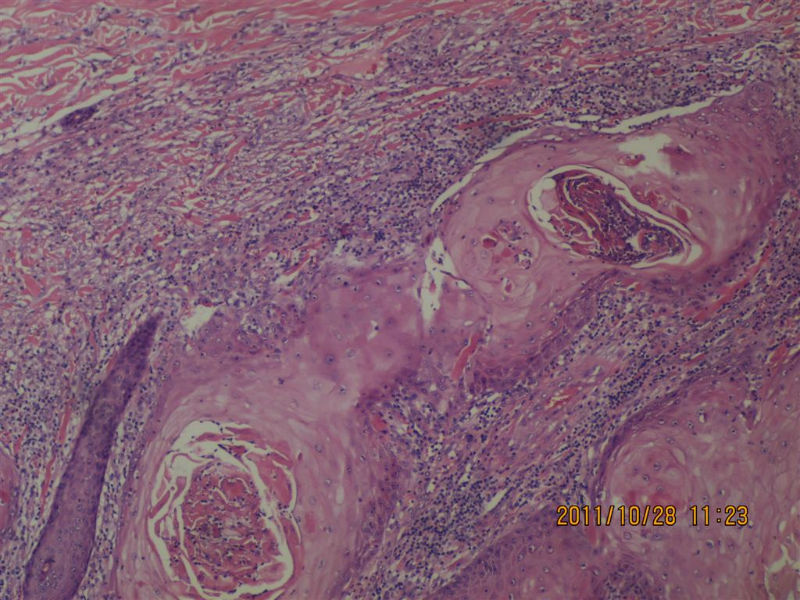

女性,71岁,右前臂肿物。角化棘皮瘤还是高分化鳞癌?

我觉得基底部还是有一些突破的,更倾向高分化鳞癌!

不知道肿物的生长速度怎样?活动度?低倍看火盆样外观、唇样边缘,底部较平整,无明显突破。更趋向于角化角化棘皮瘤。

低倍镜见表皮呈火山口样,内充满角质团块,周边上皮增生呈衣领样,底部表皮增生呈假上皮瘤样,上皮角不规则延伸至真皮,真皮大量炎细胞浸润.